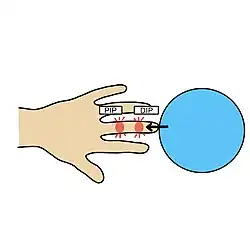

| Causes | Axial loading to the finger |

Jammed finger is a common term used to describe various types of finger joint injuries. It happens from a forceful impact originating at the tip of the finger directed towards the base. This type of directional force is called axial loading. It occurs most often when the finger is fully extended. This kind of impact can stretch or strain the ligaments in the joint beyond their normal limits. The severity of damage to the finger increases with the amount of force on the fingertip.[1] In severe cases, injury to bone may occur. When experiencing a jammed finger, the extent of injury is not always obvious and one should be evaluated by a medical professional.[2] Toes may become jammed as well, with similar results.

Jammed fingers occur from axial loading at the tip of the finger.[7] Any activity in which the fingers are outstretched could result in a jammed finger. This is particularly common in ball-related sports,[8] where forceful contact with the ball and finger tip may occur. Contact sports are also a common risk factor due to collisions between players or the ground.[7]